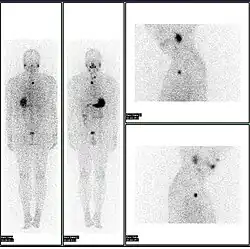

A nuclear medicine parathyroid scan demonstrates a parathyroid adenoma adjacent to the left inferior pole of the thyroid gland. The above study was performed with Technetium-Sestamibi (1st column) and iodine-123 (2nd column) simultaneous imaging and the subtraction technique (3rd column). -